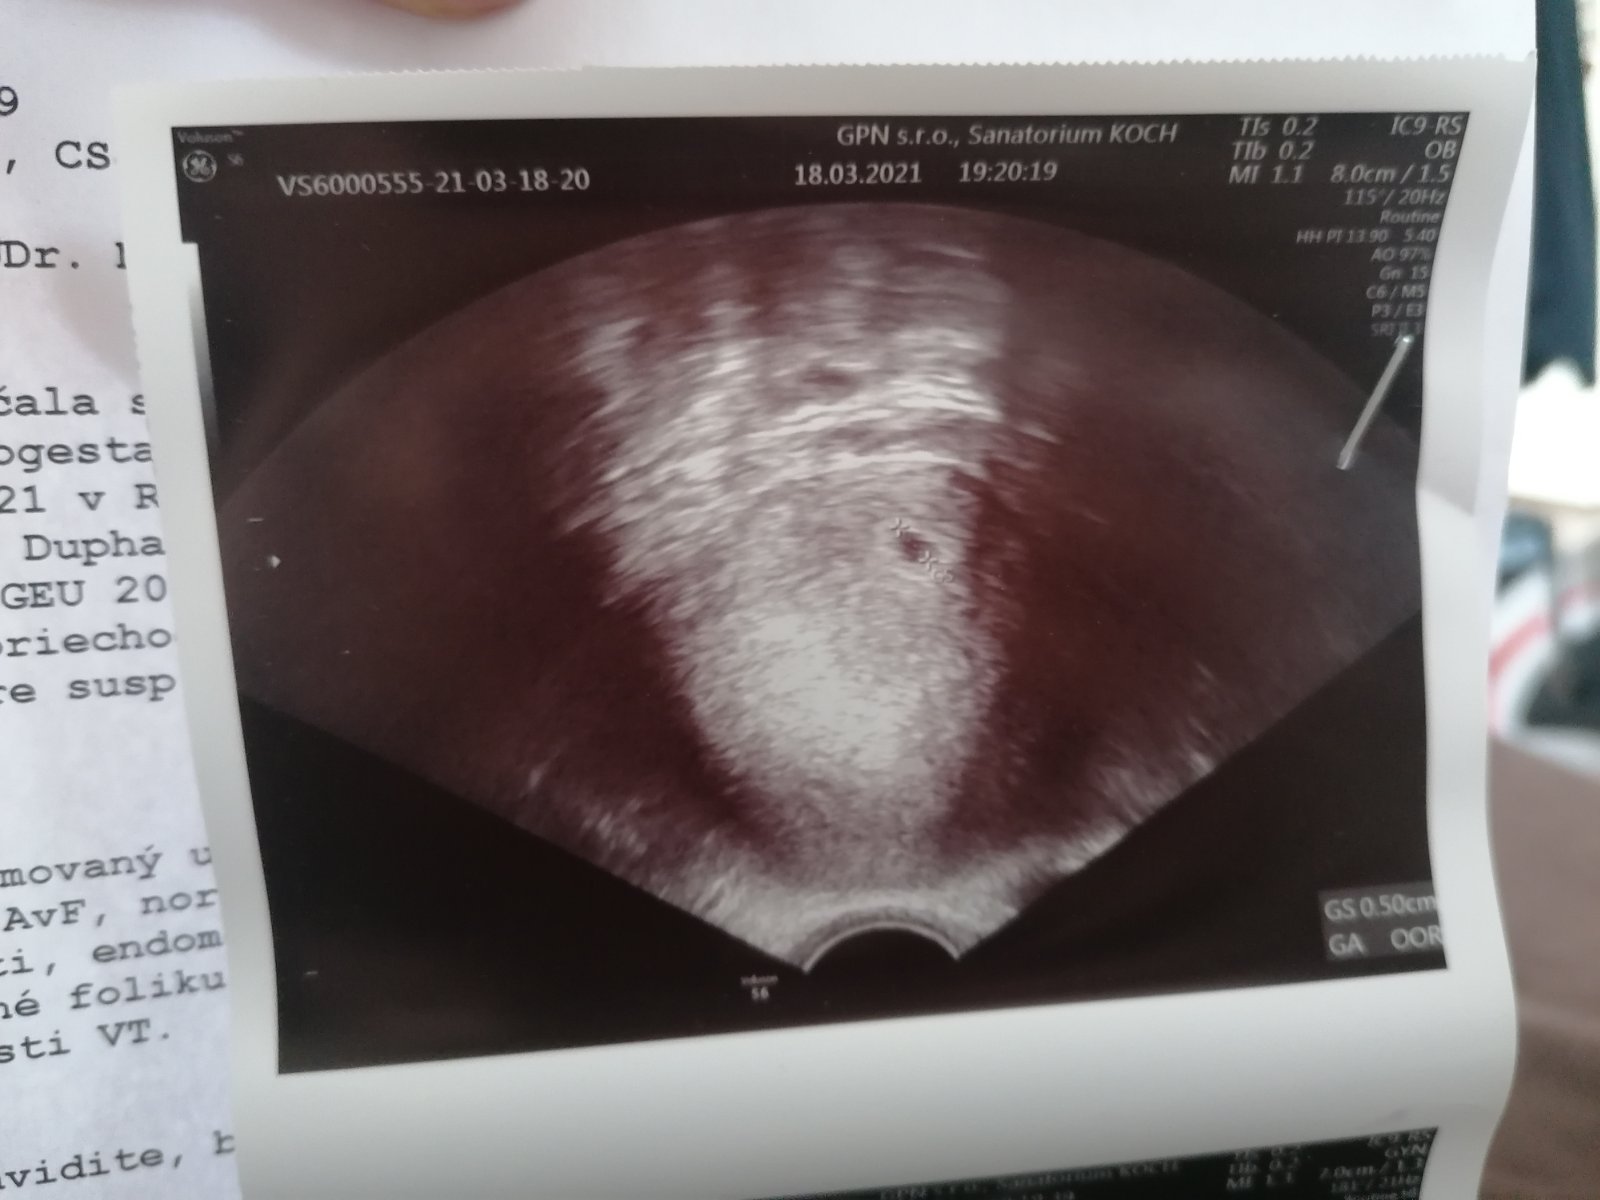

@hafanana25 ďakujem, ešte ale vraj nemáme vyhraté. Stále jemne spinim ale stále menej a boli ma bud v pravo alebo vľavo každý deň sa to strieda 😂🤦‍♀️ tak vraj uvidíme v piatok ci dačo bude na Sone zatiaľ som mala len tuto bublinku. Držím ti palce verím ze sa vám podarí. Držím nám všetkým palce musíme to dat🙏❤️

@dadaberkova Jeeej, to je cute obrázok 😍😍😍🤗🤗🤗. A ďakujem veľmi pekne, tiež by sme boli radi keby sa druhé IUI podarí,ale všetko je vo hviezdach 🤗🤗🤗😊😊😊 Teším sa na ďalší obrázok 😍